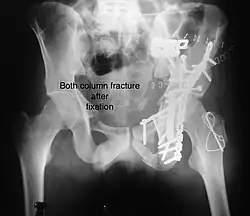

Both column fracture showing floating weight bearing dome -

Both column fracture after fixation with screws and plates -